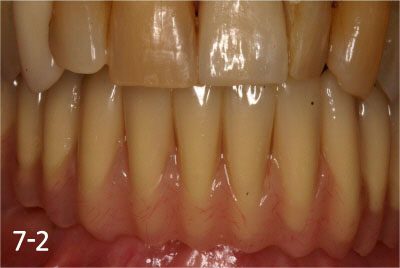

All implant crowns were fabricated and delivered. All teeth functions were restored.